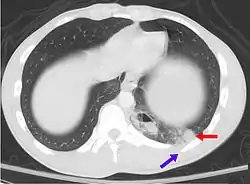

| A CT scan showing a pulmonary contusion (red arrow) accompanied by a rib fracture (purple arrow) | |